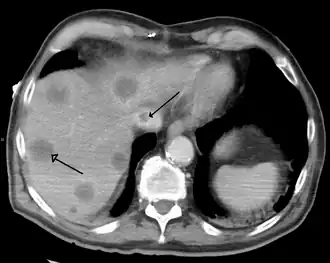

![]() | |

A gross pathology specimen of liver metastases caused by pancreatic cancer | |